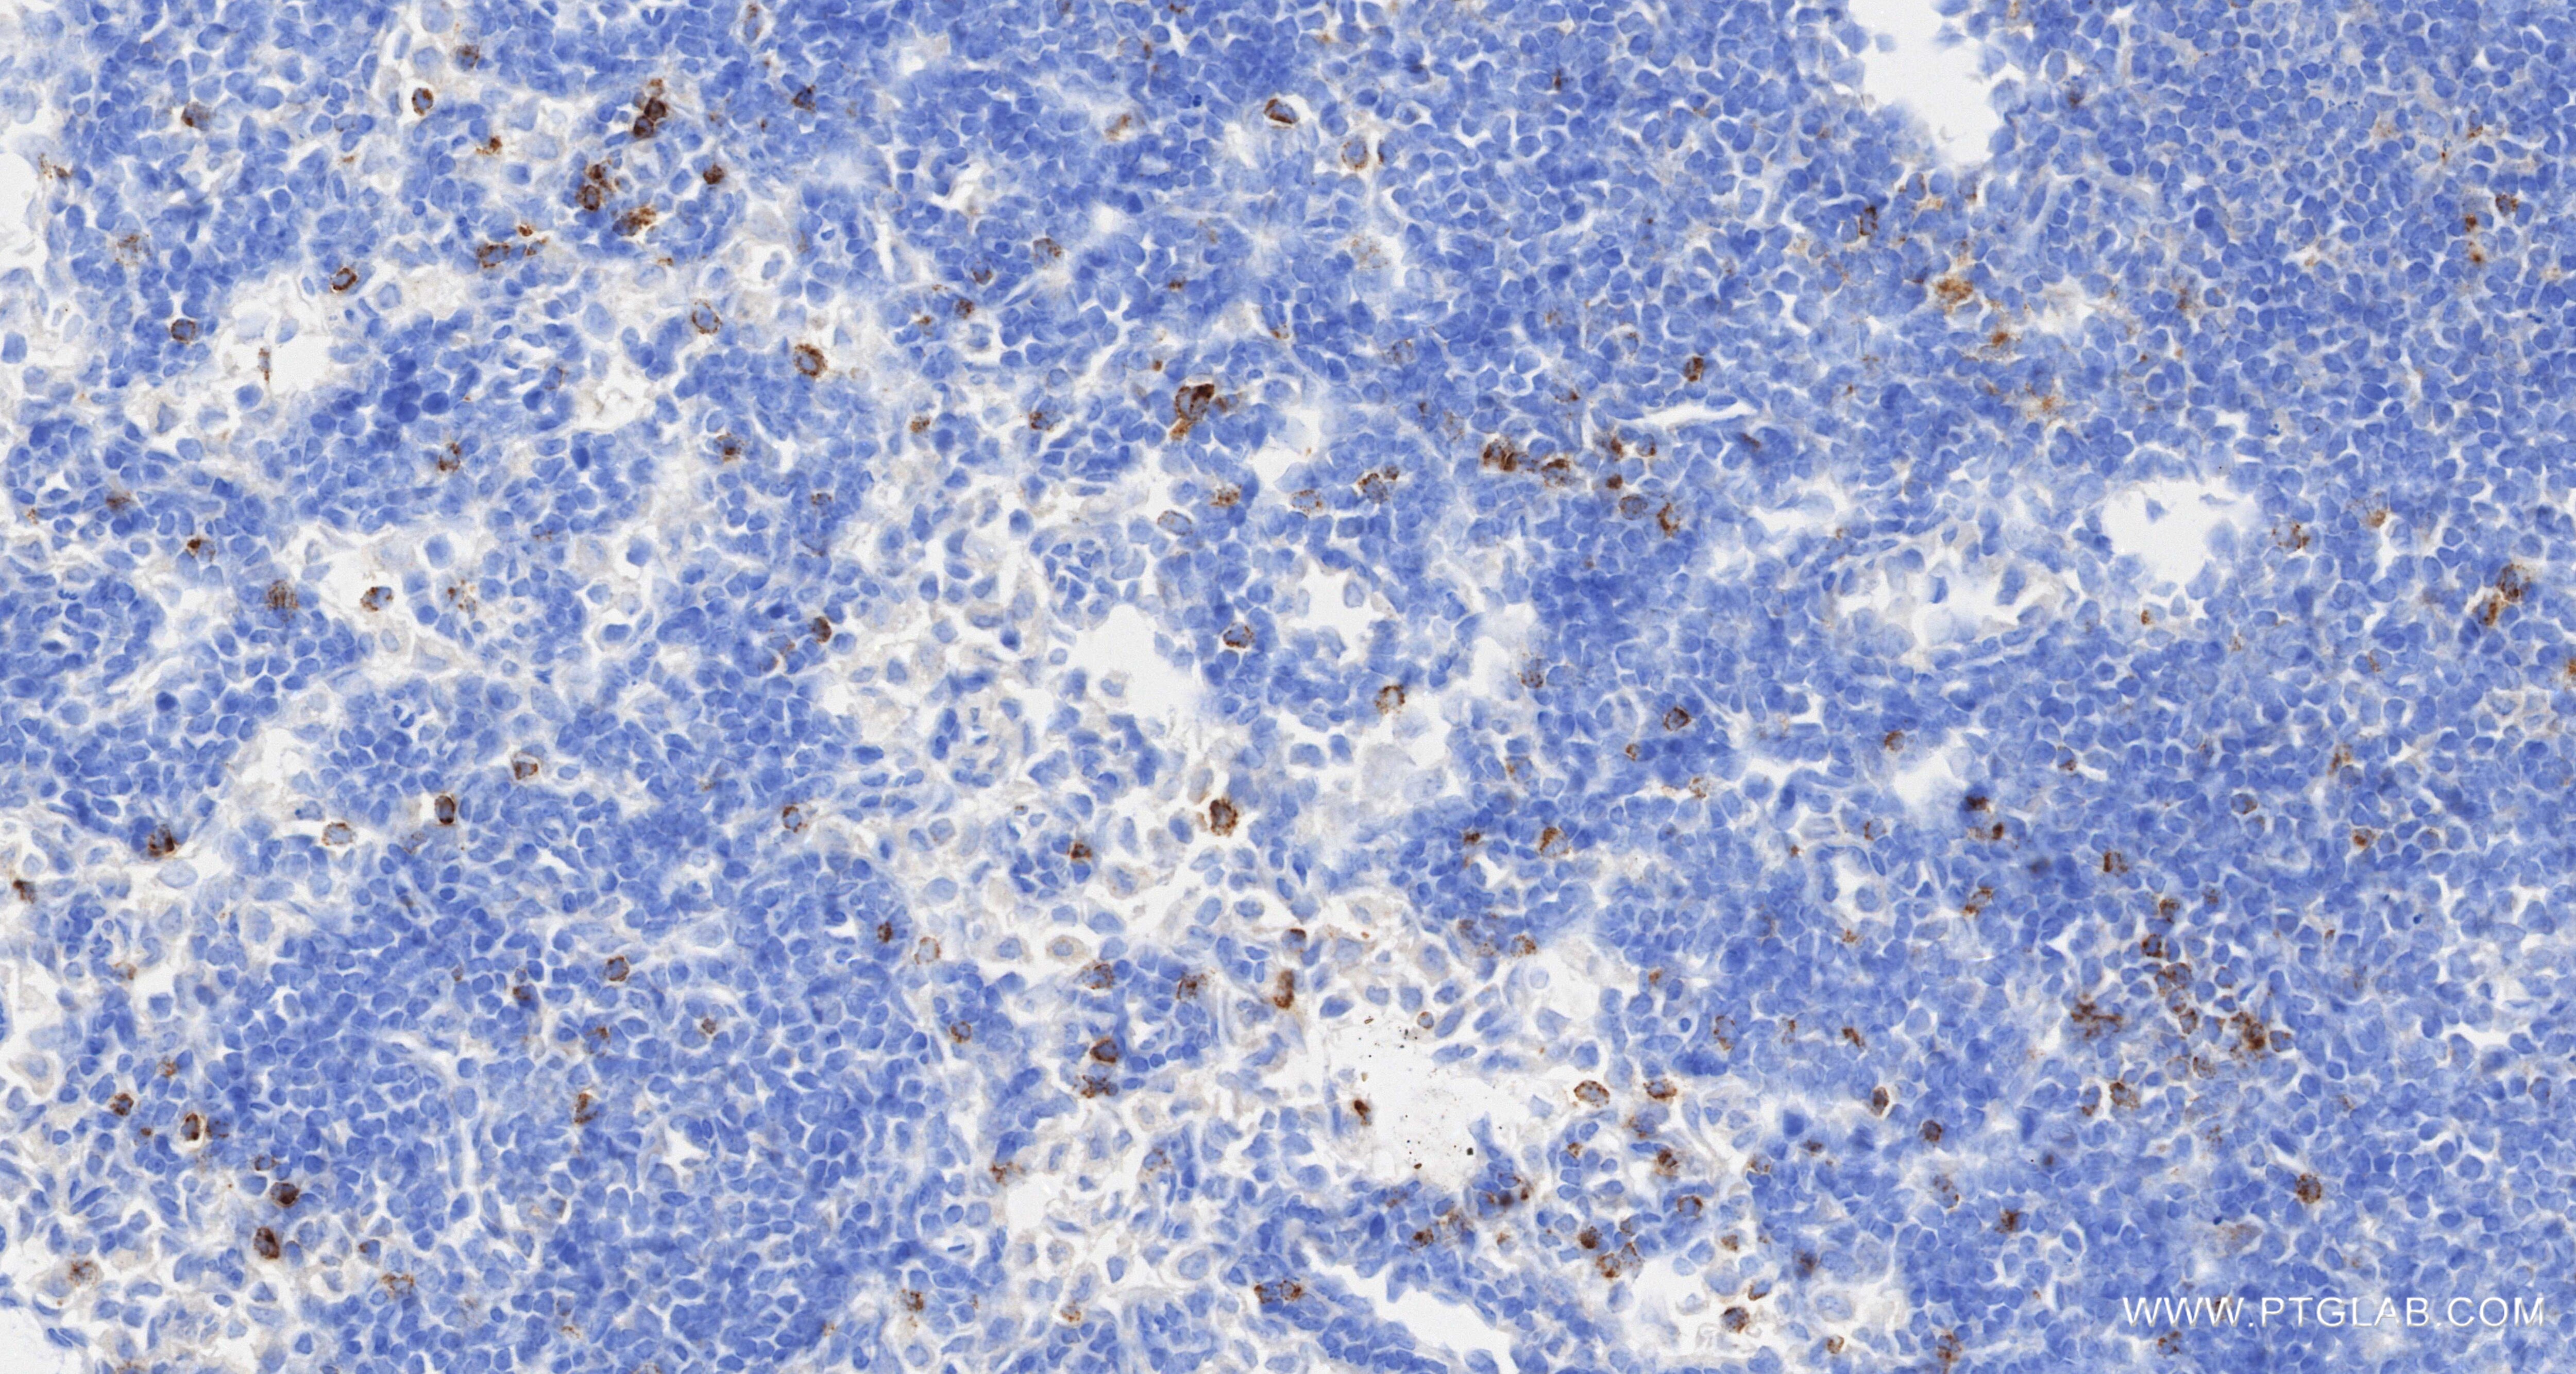

| Positive IHC detected in | mouse spleen tissue, mouse colon tissue Note: suggested antigen retrieval with TE buffer pH 9.0; (*) Alternatively, antigen retrieval may be performed with citrate buffer pH 6.0 |

| Immunohistochemistry (IHC) | IHC : 1:500-1:2000 |

87060-4-RR targets CCL5 in WB, IHC, ELISA applications and shows reactivity with mouse samples.